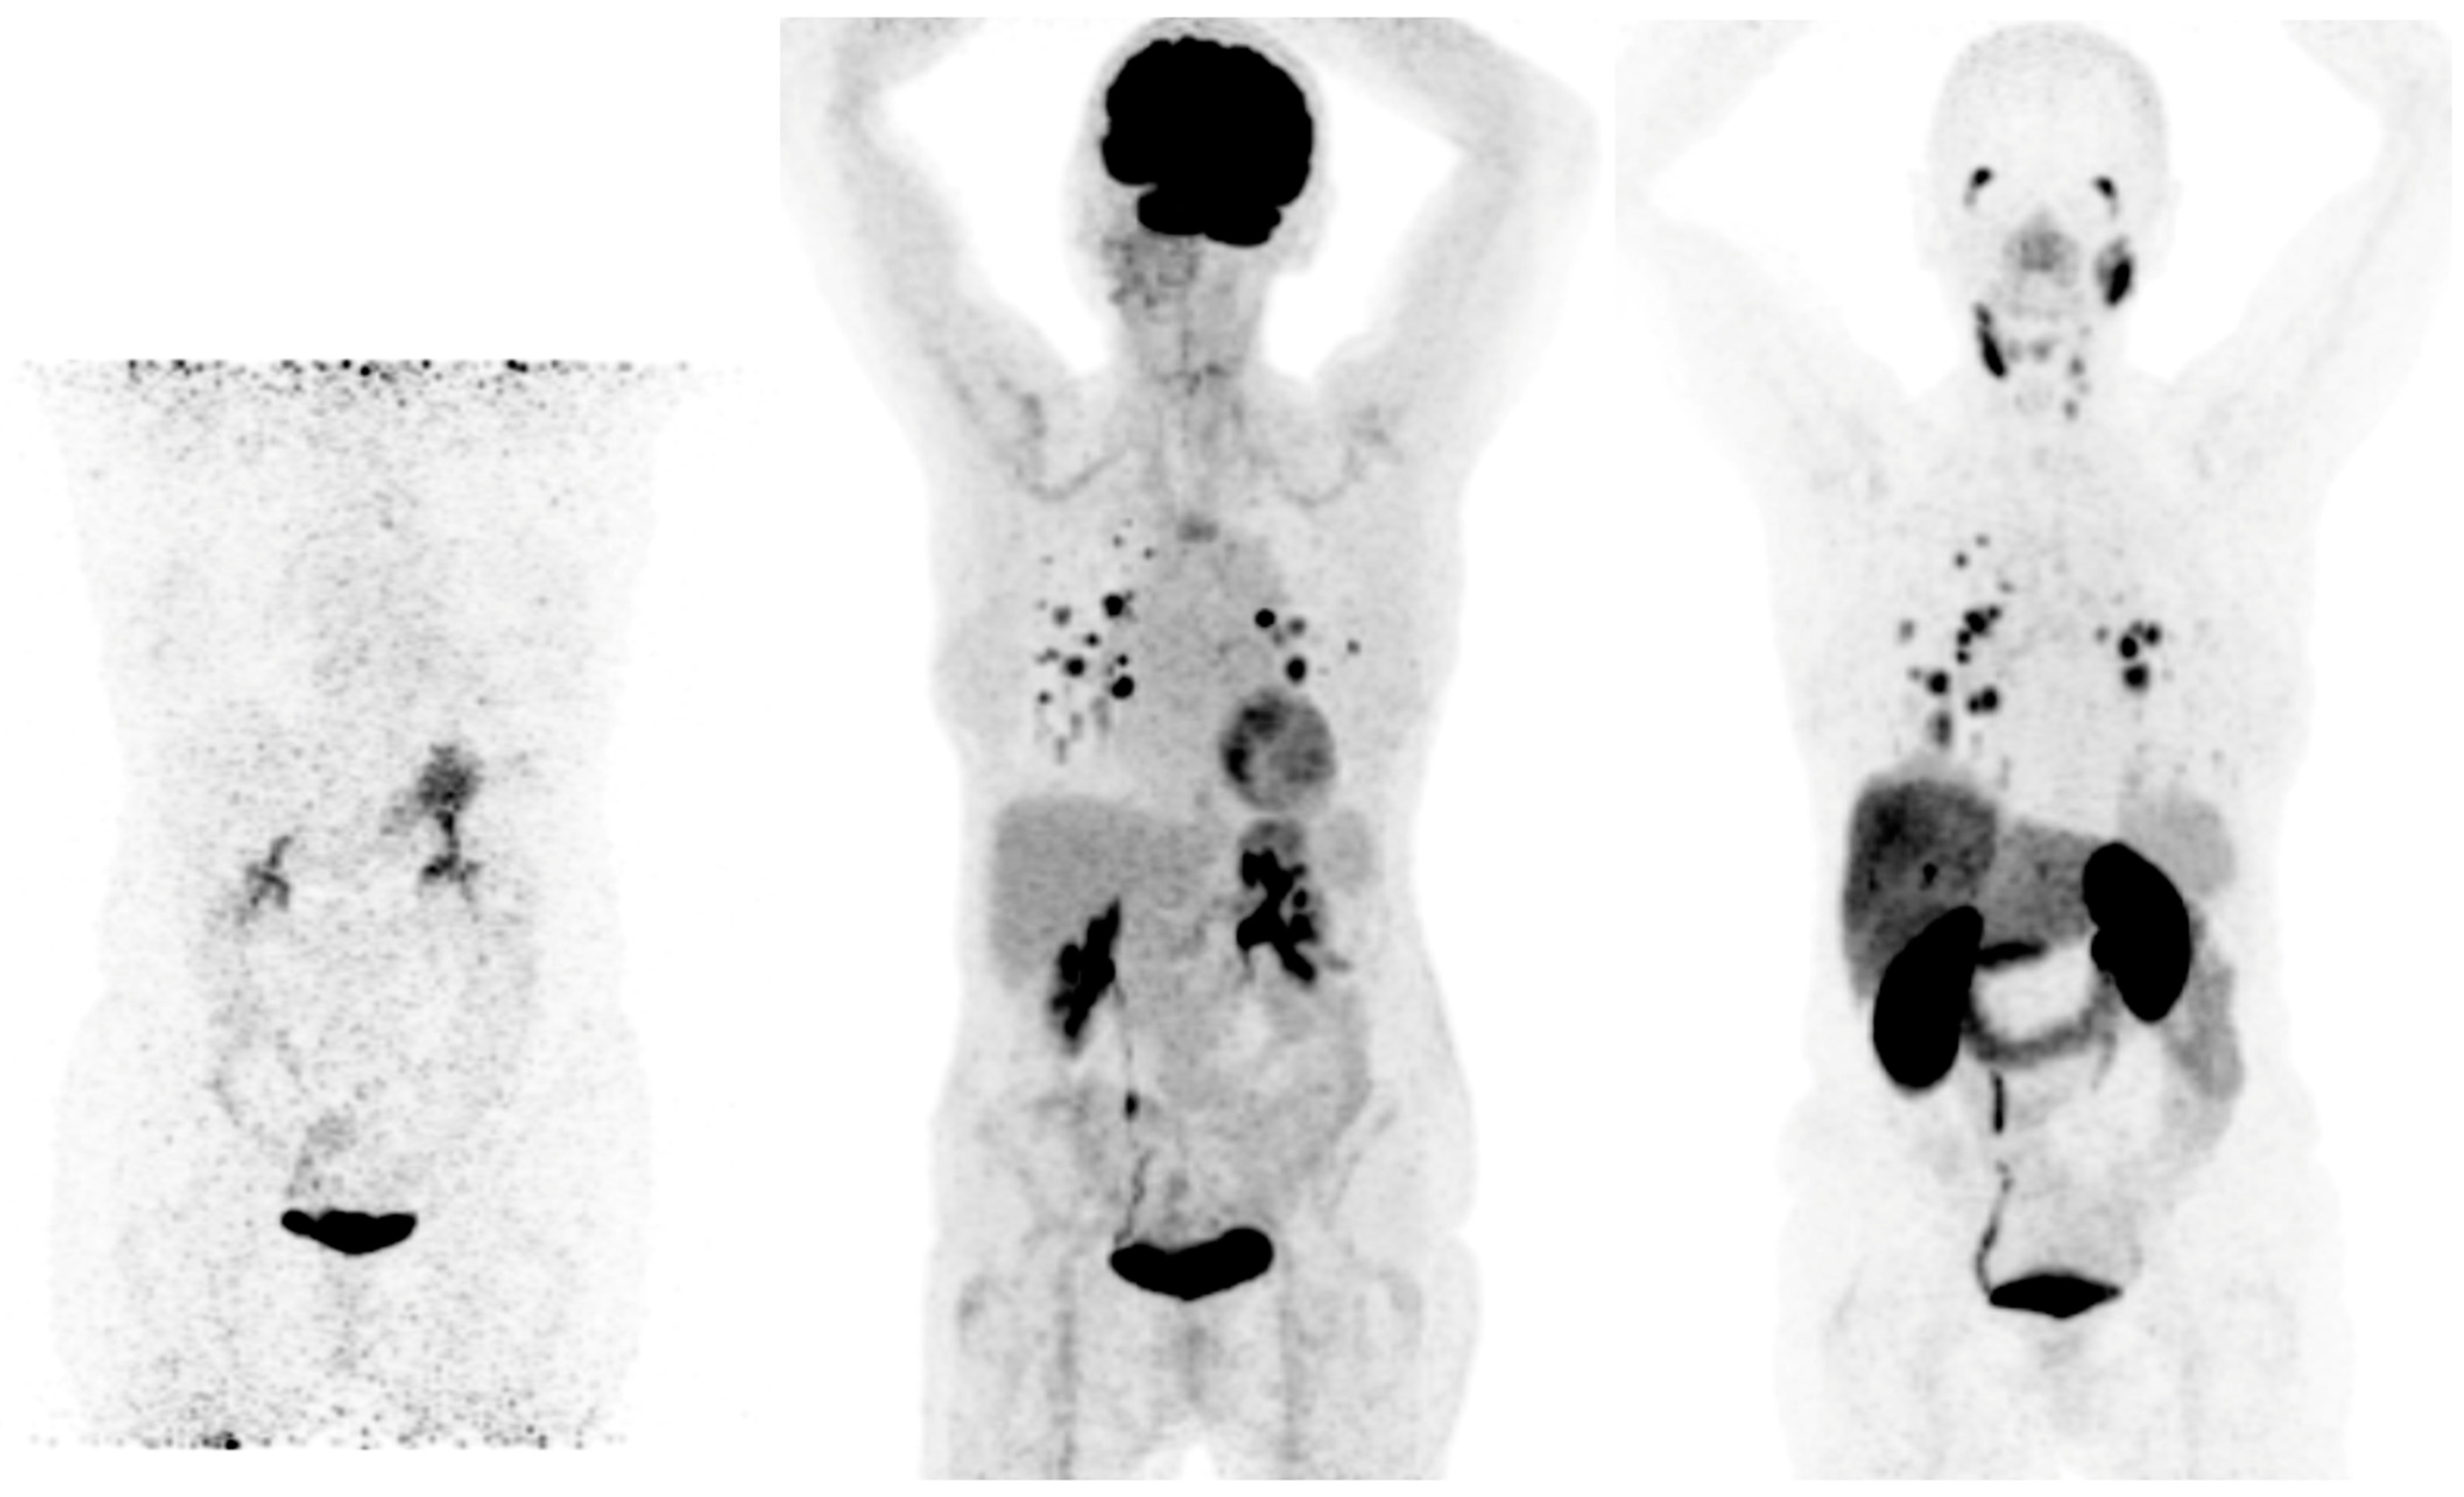

- Chen, Y.; Zheng, S.; Zhang, J.; Yao, S.; Miao, W. 68Ga-DOTA-FAPI-04 PET/CT Imaging in Radioiodine-Refractory Differentiated Thyroid Cancer (RR-DTC) Patients. Ann. Nucl. Med. 2022, 36, 610–622. [Google Scholar] [CrossRef] [PubMed]

- Fu, H.; Fu, J.; Huang, J.; Pang, Y.; Chen, H. 68Ga-FAPI PET/CT Versus 18F-FDG PET/CT for Detecting Metastatic Lesions in a Case of Radioiodine-Refractory Differentiated Thyroid Cancer. Clin. Nucl. Med. 2021, 46, 940–942. [Google Scholar] [CrossRef] [PubMed]

- Ballal, S.; Yadav, M.P.; Moon, E.S.; Roesch, F.; Kumari, S.; Agarwal, S.; Tripathi, M.; Sahoo, R.K.; Mangu, B.S.; Tupalli, A.; et al. Novel Fibroblast Activation Protein Inhibitor-Based Targeted Theranostics for Radioiodine-Refractory Differentiated Thyroid Cancer Patients: A Pilot Study. Thyroid 2022, 32, 65–77. [Google Scholar] [CrossRef]